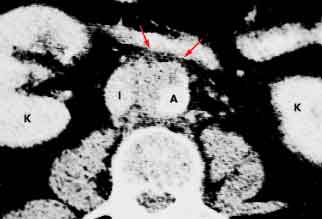

An obese 61-year-old man who had chronic obstructive pulmonary disease and sleep apnea heard a “pop” in his stomach while lifting a heavy weight; severe abdominal pain followed. In a CT scan of the abdomen and pelvis, arrows point to inflammation in the aortic wall (A) and the paraaortic retroperitoneal fat (I, inferior vena cava; K, kidney.) Calcified atherosclerotic plaques were visible, but the aorta was not dilated. There was neither retroperitoneal hematoma nor contrast extravasation to suggest rupture. The patient had aortitis.

Image courtesy of Joel M. Schwartz, MD.